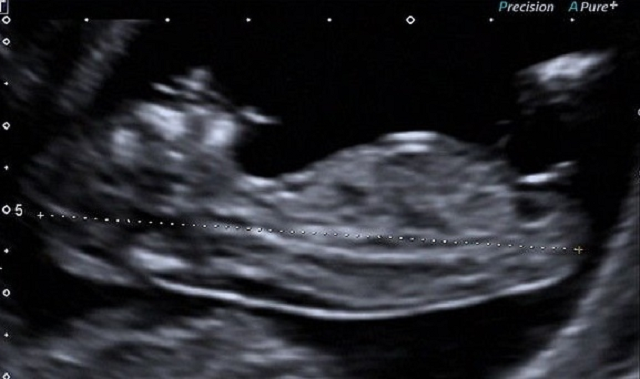

(箭头所示为正常厚度的NT)

正常情况下,NT厚度随头臀径增加而增加,打个比方,同一个胎儿13周的NT厚度比其11周时厚,而两个不同的宝宝,如果NT厚度同为3mm,则11周胎儿染色体异常几率较13周胎儿大。